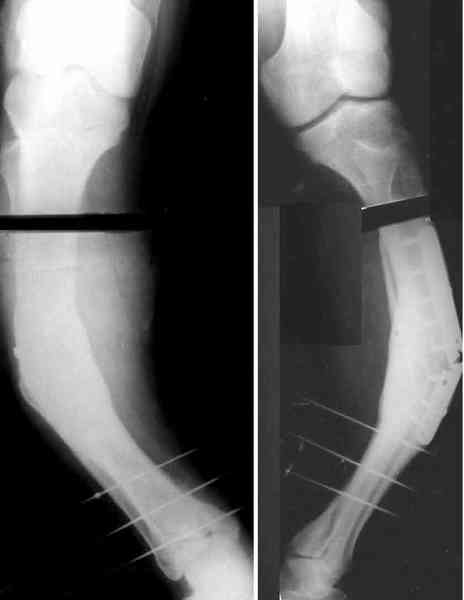

Для продолжения темы - несколько картинок.

Пациент 30 лет, лет пять назад оперирован по поводу перелома голени пластиной. Находясь на героине, нарушил режим, пошел, сломал и ногу и

пластину, но перелом сросся.

В приложении - внешний вид и рентген.

Мнения?

Лукавить не буду, я его уже вылечил. Но применил немного необычную тактику по отношению к пластине - результат после обсуждения...

Александр, как раз уровень остеотомии подробнее - на вершине деформации? Там Сломанная пластина.

Там не винты (может, плохо видно), а сломанная пластина, вросшая в кость.

Пластинку и винты мне удалось разглядеть только на профильной проекции, точнее, трехчетвертной, судя по виду коленного сустава (правый снимок). На фасной - вообще не могу разобрать, где она :( Но, в конце концов, можно и не видя ее сказать, что уровень остеотомии может быть и другим, ниже или выше пластинки, придется только компенсировать смещение по ширине, которое появится при полном устранении угла не на вершине.